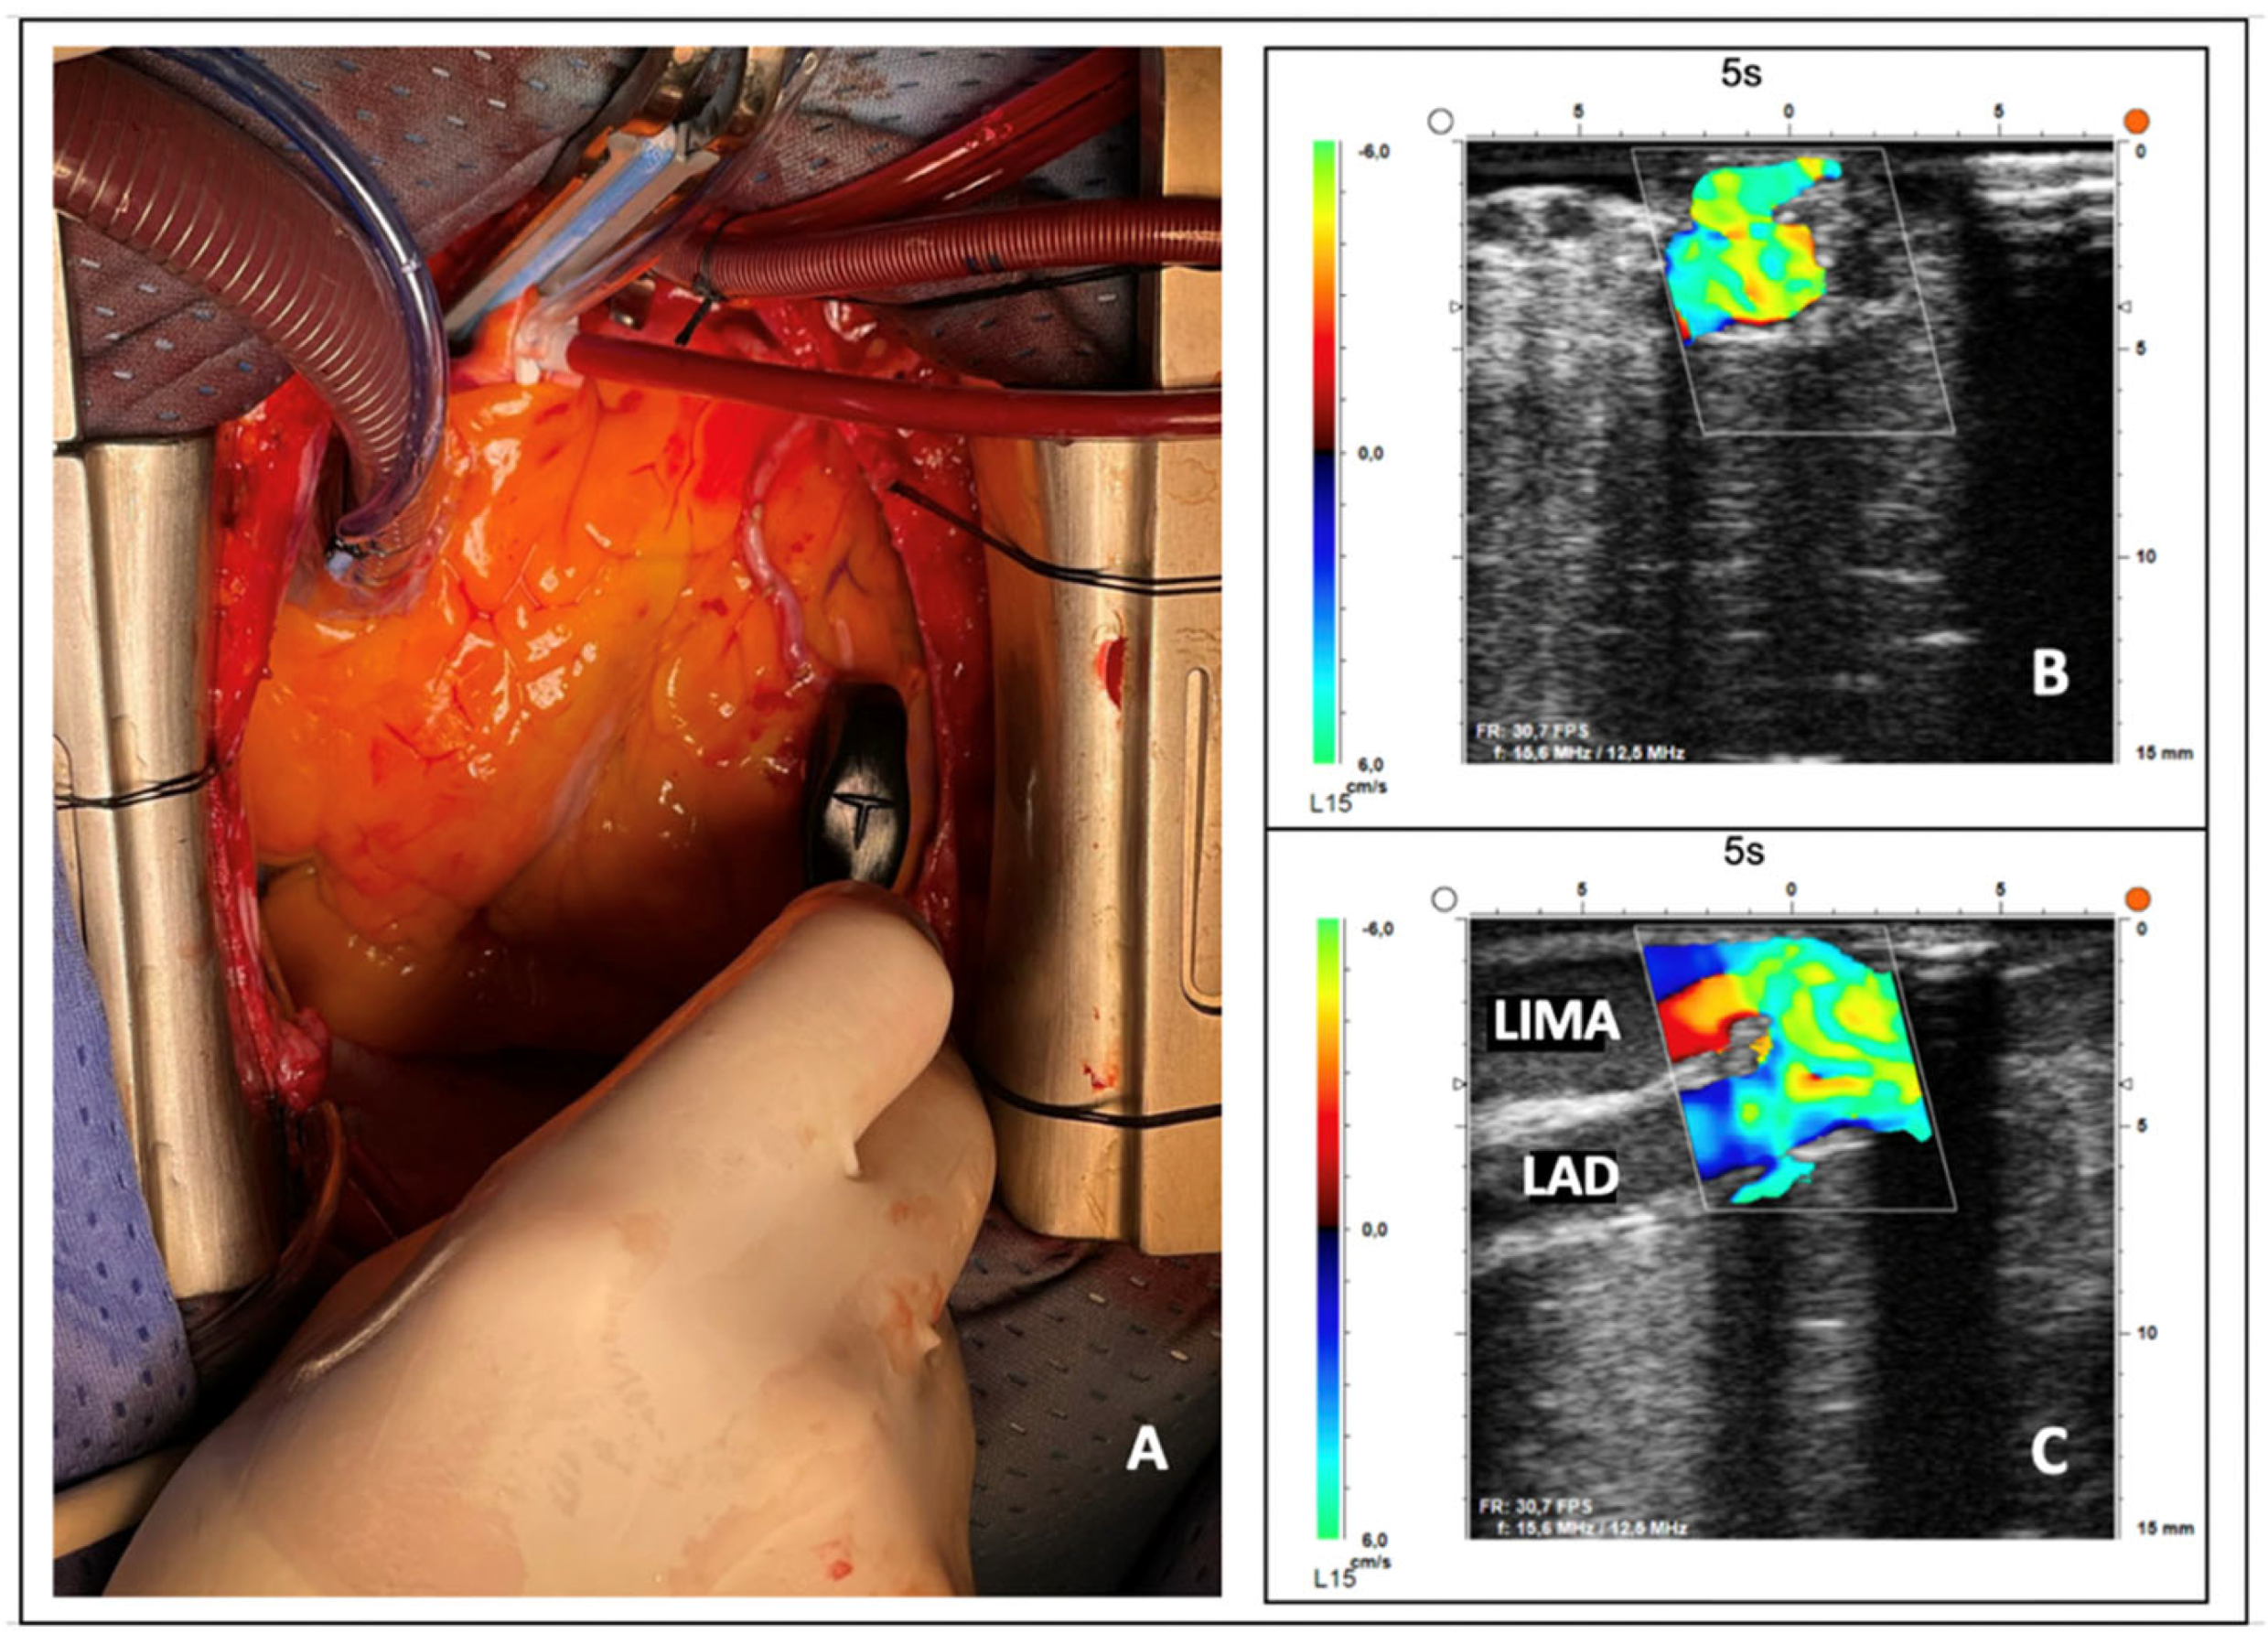

- Haaverstad, R.; Vitale, N.; Tjomsland, O.; Tromsdal, A.; Torp, H.; Samstad, S.O. Intraoperative color Doppler ultrasound assessment of LIMA-to-LAD anastomoses in off-pump coronary artery bypass grafting. Ann. Thorac. Surg. 2002, 74, S1390-4. [Google Scholar] [CrossRef]